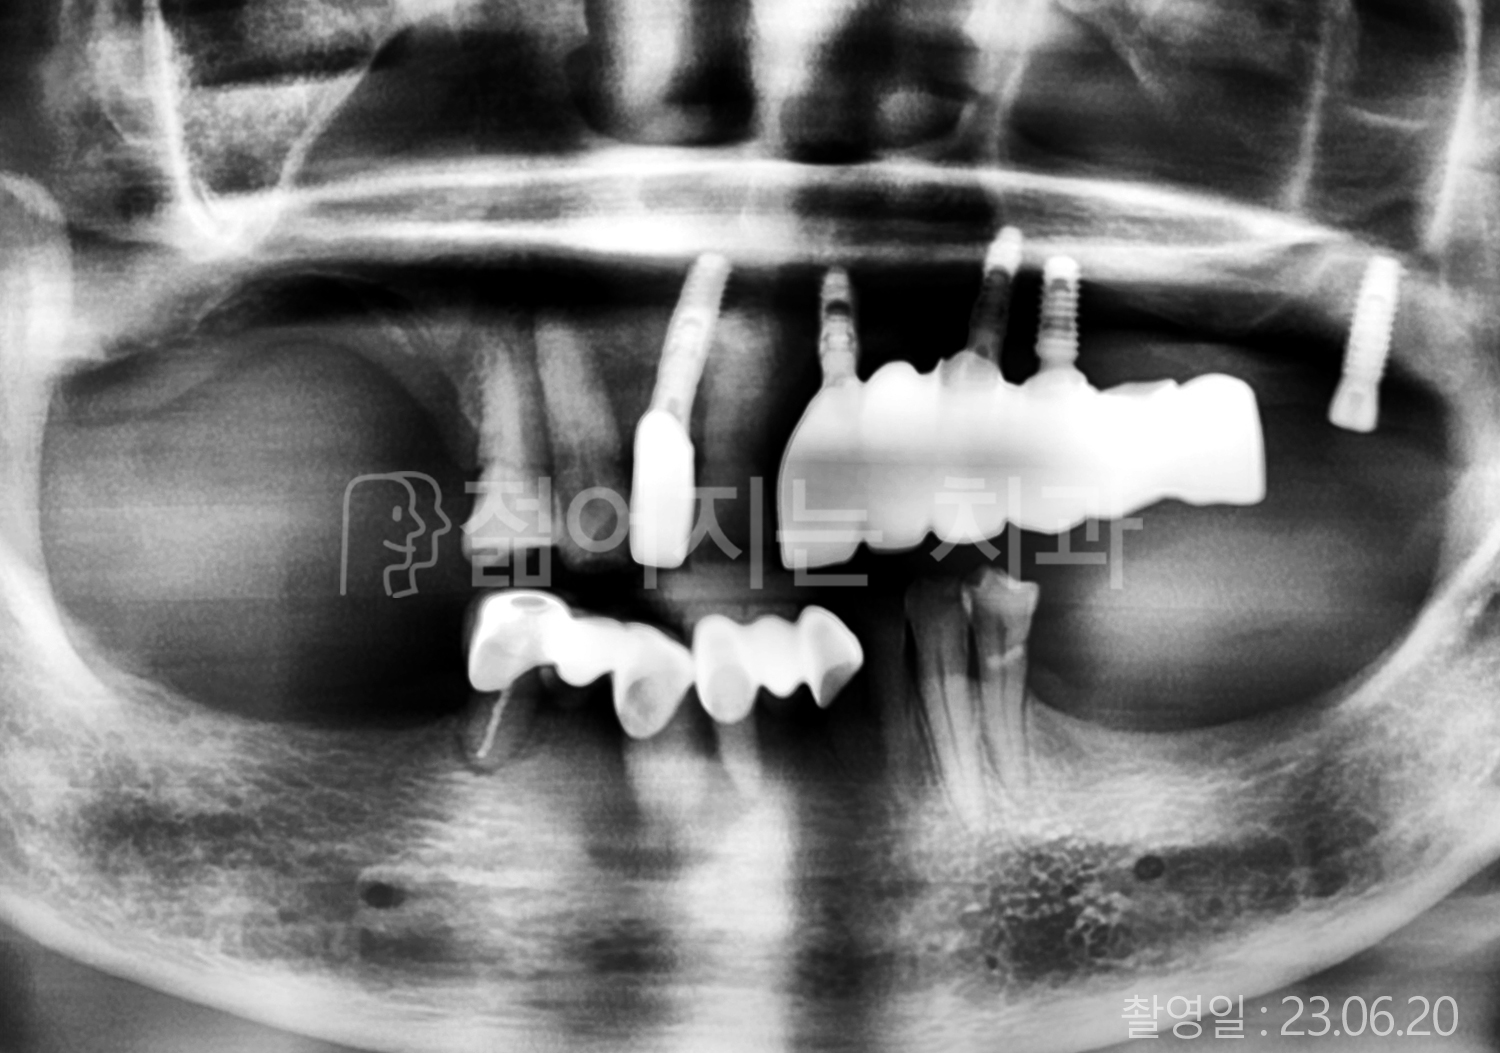

• 80대 전체치아 10개 이상 임플란트

• 60대 고혈압, 당뇨, 고지혈증 전체치아 10개 이상 임플란트

• 60대 전체치아 10개 이상 임플란트

• 60대 고혈압, 고지혈증 전체치아 10개 이상 임플란트

• 50대 고혈압, 당뇨, 고지혈증 전체치아 10개 이상 임플란트

• 70대 골다골증, 파킨스병 전체치아 10개 이상 임플란트

• 40대 전체치아 10개 이상 임플란트

• 60대 골다골증 전체치아 10개 이상 임플란트

• 40대 고혈압 전체치아 10개 이상 임플란트

• 50대 전체치아 10개 이상 임플란트

• 70대 전체치아 10개 이상 임플란트